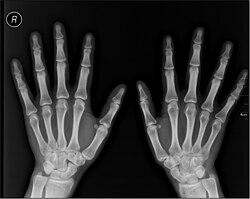

Datoteka:Dr. MacIntyre's X-Ray film.webm Radiologija je u širem značenju znanost o zračenju. Obično se pod tim nazivom podrazumijeva medicinska radiologija, odnosno grana medicine koja se bavi primjenom raznih vrsta zračenja u cilju dijagnosticiranja i liječenja stanja odnosno bolesti.

Početak medicinske radiologije se veže za otkriće zračenja koje je danas poznato pod nazivom rentgensko zračenje ili X-zrake jer ih je 1895. opisao Wilhelm Conrad Röntgen. Iako je u to vrijeme do sličnih otkrića došlo na više mjesta, Röentgen je o svojem otkriću obavijestio znanstvenu javnost pa se naziv "rentgen" ili "rendgen" uvriježio.

- Rentgenska snimanja (RTG snimke)